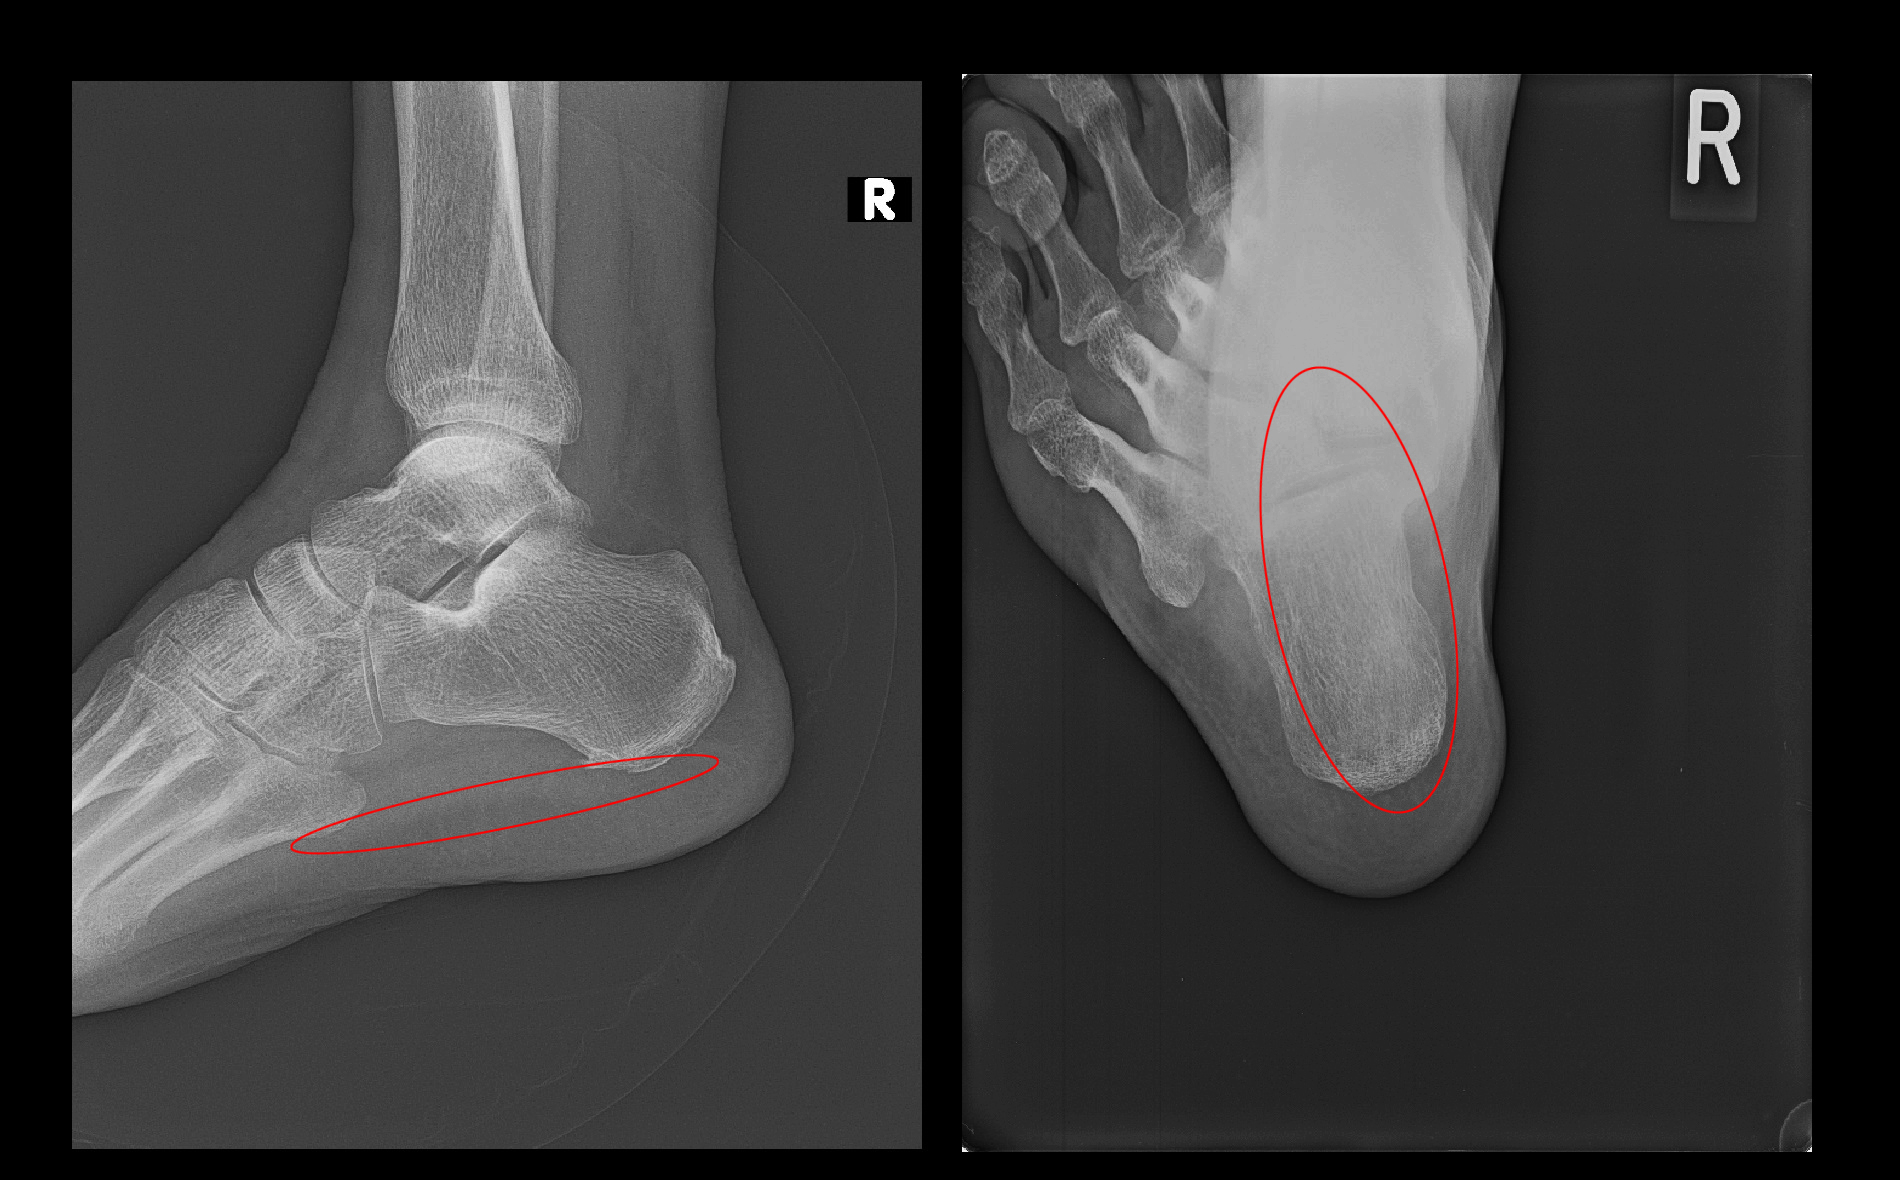

MRI検査では踵骨内の足底側が白くなり(オレンジ矢印)疲労骨折ともとれますが、痛みの本質は赤矢印の足底腱膜炎によるものと判断しました。

初診時MRI.jpg